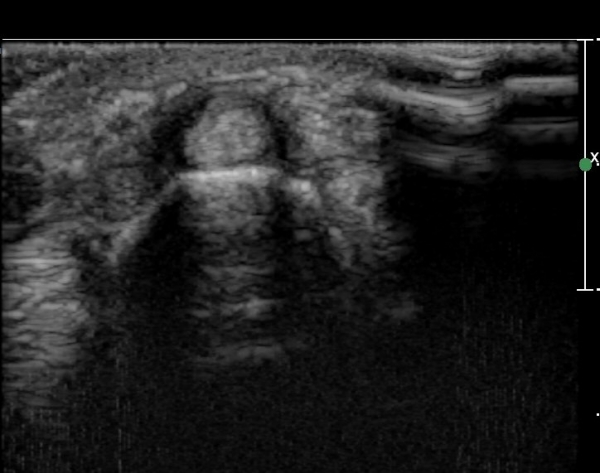

¿ä°ñ °æ»óµ¹±â ºÎÀ§¿¡¼­ tunnel I Ⱦ´Ü¸é°Ë»ç¿¡¼­ ´Ü¹«Áö½ÅÀü°Ç(EPB)ÀÇ ºÎÁ¾ ¹×

°ÇÁÖÀ§ ¼ö¾×Àú·ù°¡ °üÂûµÊ(»çÁø 1, 2)

ŽÃËÀÚ¸¦ ¾à°£ ¸»´ÜÀ¸·Î À̵¿ÇÏ´Ï ´Ü¹«Áö½ÅÀü°Ç(EPB)ÀÇ ºÎÁ¾ ¹×°ÇÁÖÀ§ ¼ö¾×Àú·ù°¡ °üÂûµÊ(»çÁø 3)

´Ü¹«Áö½ÅÀü°Ç(EPB) Á¾´Ü¸é°Ë»ç¿¡¼­ °ÇÀÇ ºÎÁ¾ ¹×°ÇÁÖÀ§ ¼ö¾×Àú·ù°¡ °üÂûµÊ(»çÁø 4)